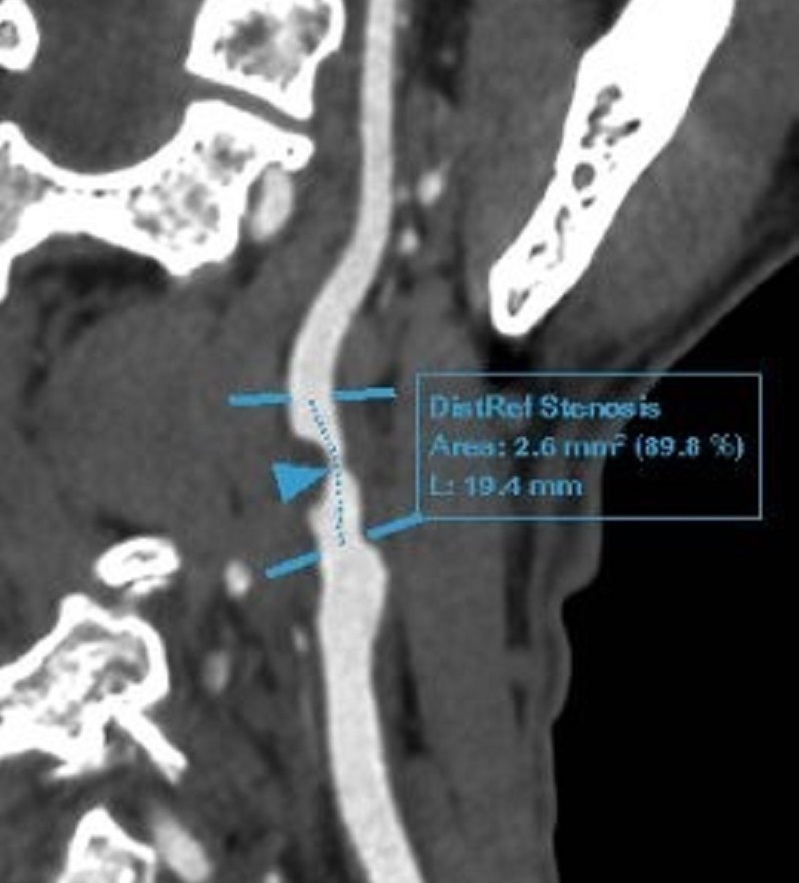

- Hẹp nặng 90% gốc động mạch cảnh trong phải, do mảng xơ vữa hỗn hợp.

Chụp cắt lớp mạch máu não phát hiện hẹp nặng 90% gốc động mạch cảnh trong phải, do mảng xơ vữa hỗn hợp

Từ kết quả khám, bác sĩ chẩn đoán xác định: Bệnh nhân mắc bệnh động mạch cảnh do xơ vữa, hẹp nặng 90% động mạch cảnh trong bên phải, lóc tách nhỏ gốc động mạch cảnh trong bên trái. Bệnh động mạch vành mạn tính. Rối loạn lipid máu.